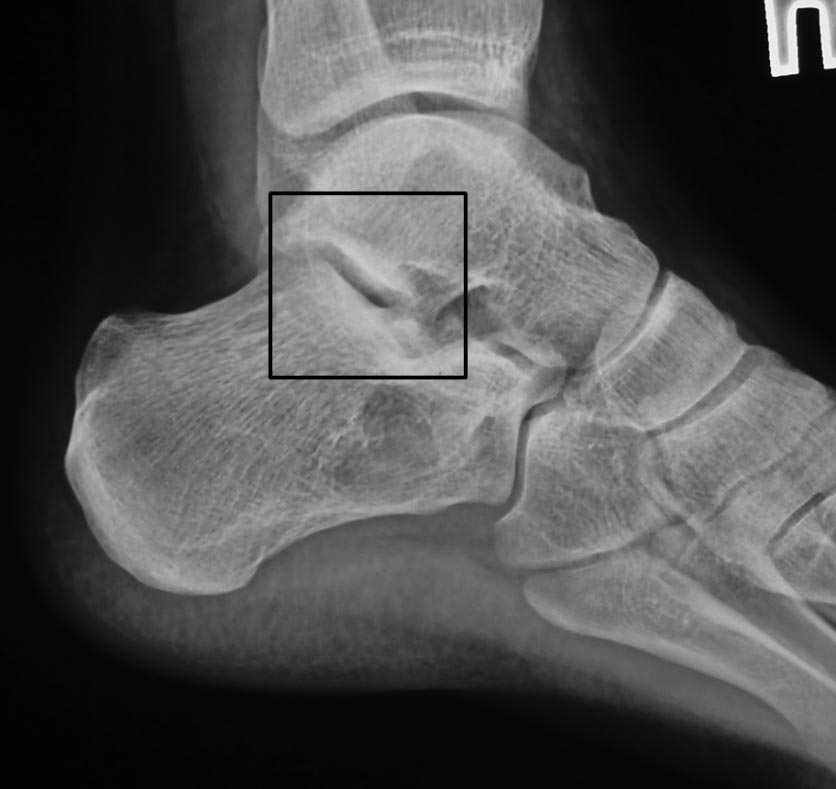

Коллеги! Делюсь первым опытом такой операции Два месяца назад потупил пациент с оскольчатым переломом таранной кости, после ДТП. При поступлении налажено скелетное вытяжение. Ниже рентгенограммы при поступлении

Во вложении всего два примера нормальных взаимоотношений в подтаранном суставе. Постарался подобрать похожие на Вашу проекции. На всех снимках выделена область, где суставные поверхности таранной и пяточной костей всегда должны быть параллельны. В Вашем случае эти линии пересекаются. Подвывих очевиден.